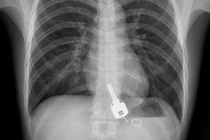

Đau ngực dữ dội, thanh niên vội đến bác sĩ và phát hiện gây sốc sau đêm say xỉn

Một thanh niên Trung Quốc phải cầu cứu bác sĩ sau khi bị đau ngực dữ dội và sốc khi biết mình nuốt phải chìa khóa nhà trong bữa nhậu với bạn tối hôm trước.

Ngày 7/6, thanh niên họ Chang, 26 tuổi, ở Quảng Đông, Trung Quốc, đi uống rượu với bạn bè nhân kết thúc một tuần làm việc dài. Khi về nhà vào lúc nửa đêm, Chang tìm chìa khóa nhưng không thấy nên đã gọi người mở cửa. Vì say rượu nên anh ta không nghĩ tới chuyện bị mất chìa khóa và đi thẳng vào giường. Sáng hôm sau, khi tỉnh, Chang bắt đầu cảm thấy đau ngực dữ dội nên tới Bệnh viện Đông Quan để kiểm tra.